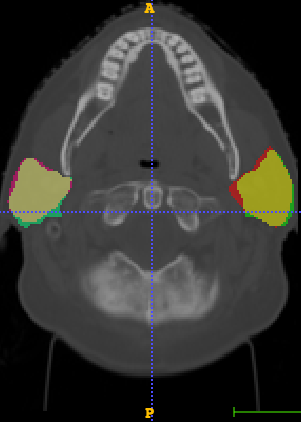

In Chapter 6, we propose an end-to-end, atlas-free 3D convolutional deep learning framework for fast and fully automated whole-volume HaN anatomy segmentation [115]. Our deep learning model, called AnatomyNet, segments OARs from head and neck CT images in an end-to-end fashion, receiving whole-volume HaN CT images as input and generating masks of all OARs of interest in one shot. AnatomyNet is built upon the popular 3D U-net architecture, but extends it in three important ways: 1) a new encoding scheme to allow auto-segmentation on whole-volume CT images instead of local patches or subsets of slices, 2) incorporating 3D squeeze-and-excitation residual blocks in encoding layers for better feature representation, and 3) a new loss function combining Dice scores and focal loss to facilitate the training of the neural model. These features are designed to address two main challenges in deep-learning-based HaN segmentation: a) segmenting small anatomies (i.e., optic chiasm and optic nerves) occupying only a few slices, and b) training with inconsistent data annotations with missing ground truth for some anatomical structures. We collect 261 HaN CT images to train AnatomyNet, and use MICCAI Head and Neck Auto Segmentation Challenge 2015 as a benchmark dataset to evaluate the performance of AnatomyNet. The objective is to segment nine anatomies: brain stem, chiasm, mandible, optic nerve left, optic nerve right, parotid gland left, parotid gland right, submandibular gland left, and submandibular gland right. Compared to previous state-of-the-art results from the MICCAI 2015 competition, AnatomyNet increases Dice similarity coefficient by 3.3% on average. AnatomyNet takes about 0.12 seconds to fully segment a head and neck CT image of dimension , significantly faster than previous methods. In addition, the model is able to process whole-volume CT images and delineate all OARs in one pass, requiring little pre- or post-processing. We demonstrate that our proposed model can improve segmentation accuracy and simplify the auto-segmentation pipeline. These contributions are released as an open-source software package called AnatomyNet, which is publicly available555https://github.com/wentaozhu/AnatomyNet-for-anatomical-segmentation. Portions of this chapter were published as part of [115].

- [121] W. Zhu and X. Xie. Adversarial deep structural networks for mammographic mass segmentation. arXiv:1612.05970, 2016.